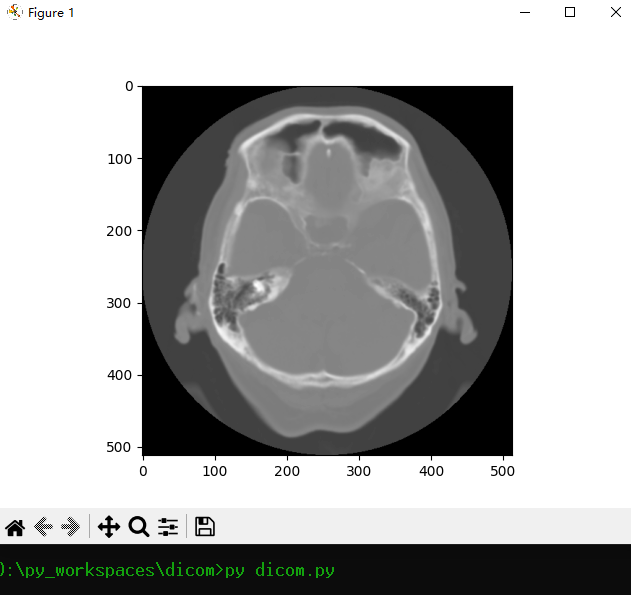

## 3.将 dcm文件 从数据库中读取并显示·

```python

# 连接到MySQL数据库

cursor = conn.cursor()

cursor.execute("select file_data from dicom_files ")

result = cursor.fetchone()

blob_data = result[0]

dataset = dcmread(BytesIO(blob_data))

image_data = dataset.pixel_array

# 显示DICOM图像

plt.imshow(image_data, cmap=plt.cm.gray)

plt.show()

cursor.close()

conn.close()

```

## 4.运行

最后运行程序

py dicom.py